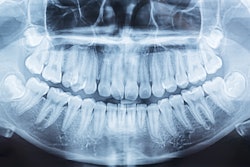

It is U.S. Patent No. 11,676,701 and is entitled “Systems and Methods for Automated Medical Image Analysis." The patent grants Pearl exclusive rights to the computer system technology supporting the application programming interface of Second Opinion and covers the machine-learning models used to generate and train image data depicting dental radiographs.